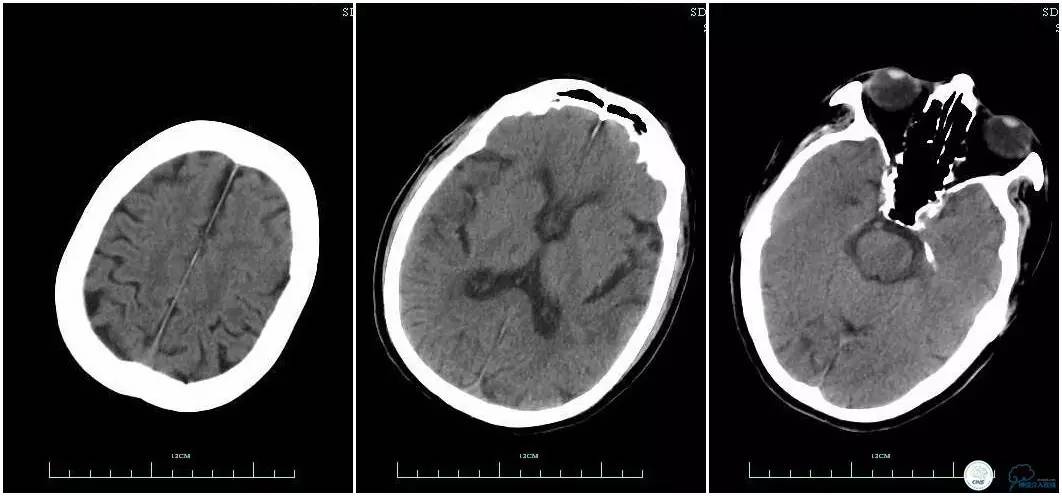

辅助检查:血常规、生化、凝血功能未见明显异常,心电图:窦性心律,ST-T改变;头颅CT平扫:未见明显出血。头颅MRI:未见新鲜梗塞灶;头颅MRA:双侧大脑前动脉远端缺如。

术前头颅CT平扫。

术前头颅MRI。